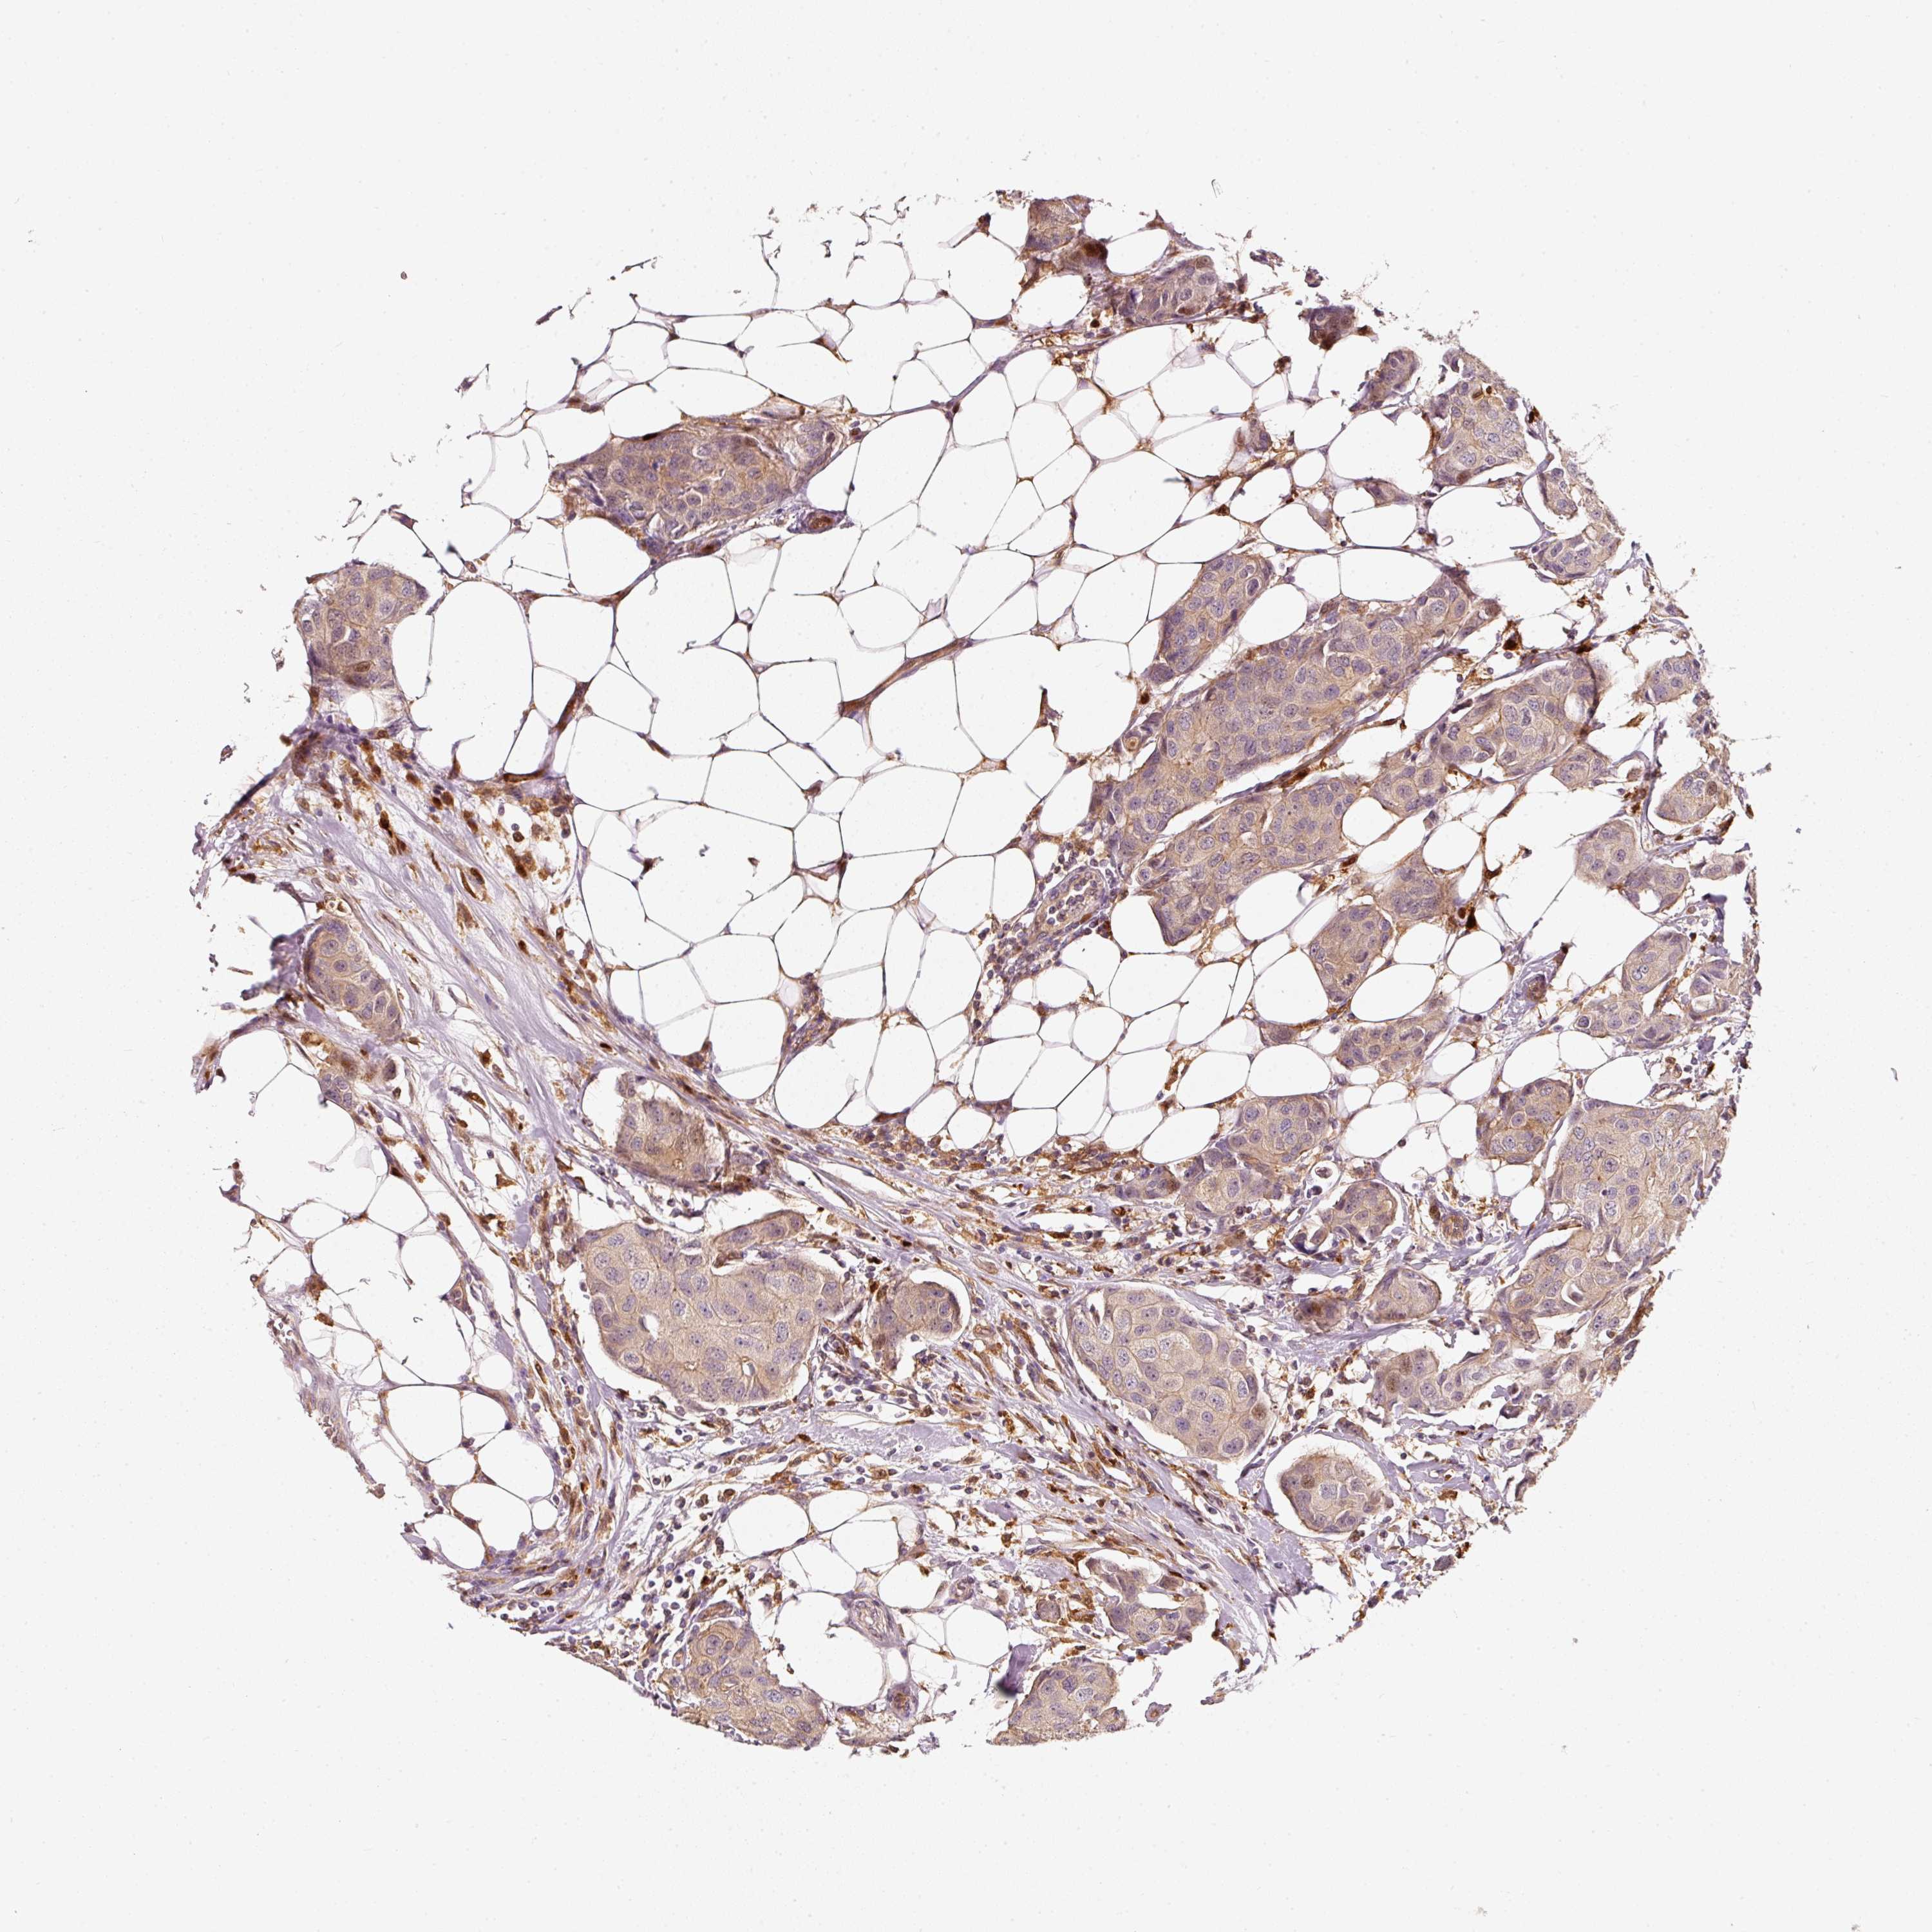

CANCER BREAST CANCER Show tissue menu

BRCA TCGA BRCA VALIDATION PROTEIN EXPRESSION